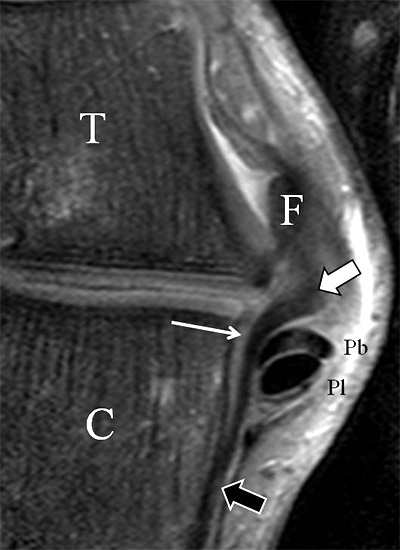

Ligamentum fibulocalcaneare (LFC)

Der Ursprung des Ligamentum fibulocalcaneare liegt unmittelbar kaudal und dorsal des Ursprungs des Ligamentum fibulotalare anterius, so dass gehäuft kombinierte Verletzungen und auch ein gemeinsamer knöcherner Ausriss beobachtet werden. Nach kaudal dorsal verläuft das Band dann nach medial konvex unter die Peroneussehnen. Danach ist ein schräg deszendierender, gestreckter Verlauf bis zum calcanearen Ansatz abgrenzbar (Abb. 10). Dieser zu allen drei Standardebenen schräge Verlauf erschwert häufig die Diagnostik des LFC vor allem bei subtileren Verletzungen. Spezialprojektionen, die dem Bandverlauf orthograd folgen (entweder schräg coronar oder schräg sagittal) erleichtern auch hier die Diagnostik (Abb. 11) insbesondere nicht dislozierter Avulsionen. Assoziierte Verletzungen der Peroneussehnenloge müssen mit beurteilt werden, wobei neben Verletzungen der Sehnen und Sehnenscheiden die Beurteilung des Retinaculum peroneum superius und inferius wichtig ist. In einem Kollektiv von Patienten mit chronischen Außenbandinstabilitäten weisen 50% der Patienten eine Verletzung dieser Strukturen auf 5. Auch hier erleichtern hochauflösende Techniken die Diagnostik (Abb. 12).